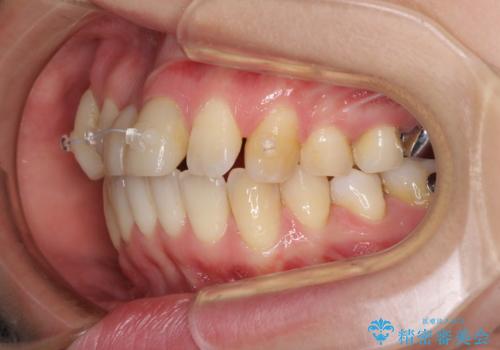

- 転倒により前歯の一部が欠けてしまったとのことで来院された患者様です。

神経が保存できる歯、神経を除去しなければならない歯、抜歯が必要な歯があり、ブリッジやインプラントなどによる治療を提案しました。

元々歯並びが気になっていたとのことで、前歯の治療を行うことを契機に矯正治療も行うこととしました。

本来であれば積極的に小臼歯を抜歯して口元を下げても良いのですが、前歯を1本抜歯しないといけなくなったため、非抜歯矯正をインビザラインを用いて行うこととしました。

補助装置により上顎歯列を遠心移動させたため、非抜歯でしたが口元の突出感をある程度改善させることができました。